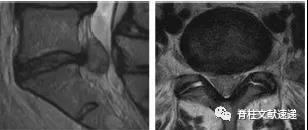

图注:49岁男性,极外侧腰椎间盘突出症。

图注:49岁男性,极外侧腰椎间盘突出症,有黑色素瘤病史。(e) 轴位PET图像显示病灶部位有FDG摄取,怀疑黑色素瘤转移。经过3周的保守治疗,病人的病情有所好转。临床上并没有黑色素瘤诊断。